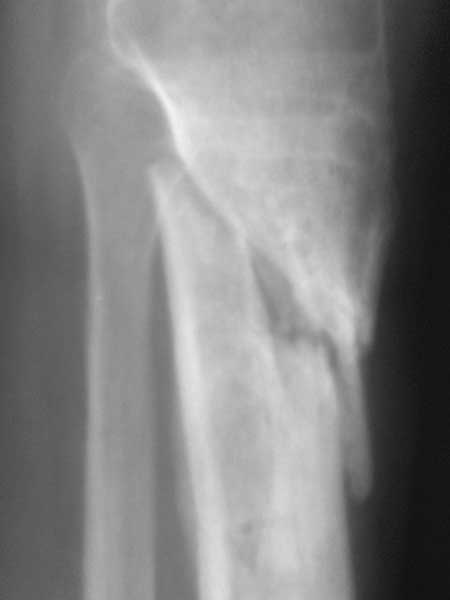

Важны мнения опытных докторов владеющих интрамедуллярным остеосинтезом. Пациент 50 лет.В анамнезе з/оскольч.перелом в/з-с/3 б/б кости. Был в АВФ 9 мес, демонтирован по его словам по поводу спицевой инфекции.также был со слов вскрыт гнойник на передней поверхности голени в зоне ложняка. на данный момент клинически: патол.подвижность в в/з голени и заживающая рана 0,2*4см по передней поверхности голени в зоне ложняка с скудно-умеренным серозным отделяемым( скорее вне зоны проведения спиц). Подвижность -умереннная. Трофических и сосудистых нарушений можно сказать нет. Сгибание в коленном суставе возможно без насилия ок. 50град. Вопрос - как делать? Нам предстваляется два пути: 1.Не дожидаясь заживления раны о/с АВФ,с открыванием ложняка: почистить его+ остеотомия малобрецовой ближе к н/3-с/3 границе. 2.перевязывать рану, после заживления подождать недельки две. Паралельно разрешить приступать на конечность. 2.1Если гной будет то см.вариант1.

2.2 Если гноя нет возможна ли установка штифта ???Т.к. 1) верхнее плечо перелома короткое 2) Риск сломать осколки при штифтовании в связи с разрушением эндостальной мозоли 3) угроза инфицирования, конечно если нагноится то опять см. вар.1. Есть конечно варианты штифта с антибиот покрытием, но это не панацея. У кого был такой опыт поделитесь пожалуйста наблюдениями( лучше с проиллюстрированными R)

Жаль, что нет фасной проекции. Перелом на 2 уровнях, есть искривление костно-мозгового канала. Проксимальный отломок короткий. Вывод: лучше не штифтовать.

3.Перелом на 2 уровнях, есть искривление костно-мозгового канала. Проксимальный отломок короткий.

Ни одного снимка, где было бы видно коленный сустав.. Не совсем понимаю столь яростное отрицание стержня, проксимальный отломок не так уж и короток, 3 разнонаправленных винта войти смогут. Учитывая продление на диафиз, если выбирать между здоровенной пластиной и стержнем, ИМХО целесообразнее стержень.